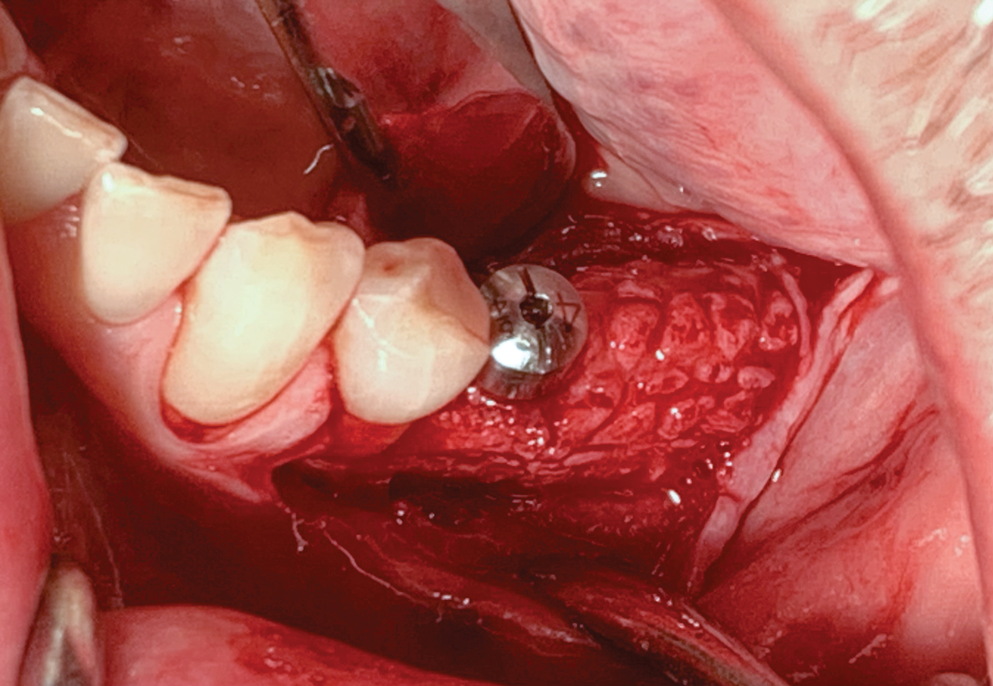

Fig 3. Premolar extracted and flap release.

Figure 3

The patient received amoxicillin 500 mg 3 times a day for 10 days, starting the day before surgery.13,14 A full-thickness flap was elevated, extending from tooth No. 22 to at least one tooth mesial and distal to the mesh placement area (Figure 3). Although a vertical releasing incision was not necessary mesially, one can be made to allow sufficient tissue and ensure tension-free closure. It is important that the vertical incision does not end at the joint between the host bone and mesh. The periosteum in this case was left intact and no superficial release of the mylohyoid lingual was necessary.3,15,16